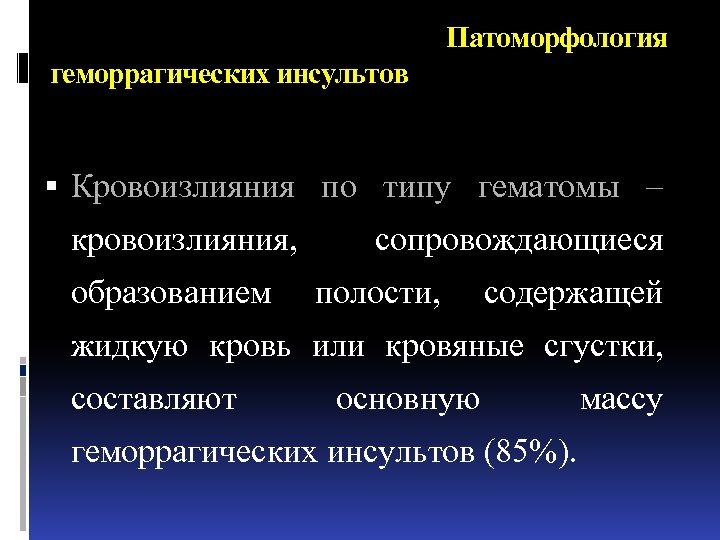

Патоморфология геморрагических инсультов Кровоизлияния по типу гематомы – кровоизлияния, образованием сопровождающиеся полости, содержащей жидкую кровь или кровяные сгустки, составляют основную геморрагических инсультов (85%). массу

Патоморфология геморрагических инсультов Кровоизлияния по типу гематомы – кровоизлияния, образованием сопровождающиеся полости, содержащей жидкую кровь или кровяные сгустки, составляют основную геморрагических инсультов (85%). массу